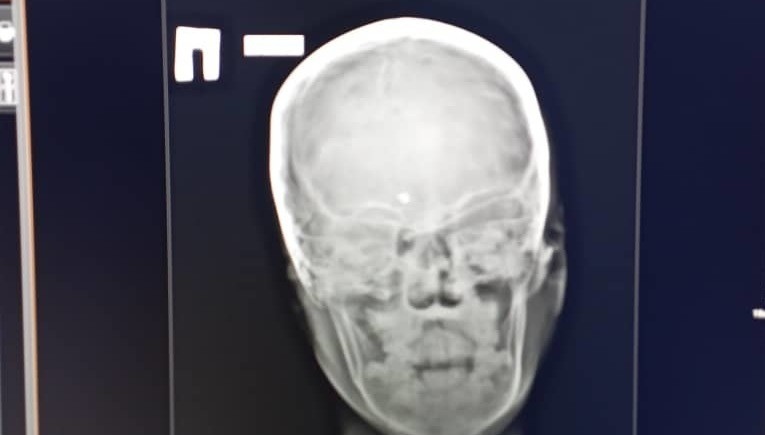

9yo boy with bullet stuck in his brain discharged from hospital

AKIPRESS.COM - A nine-year-old child, who received a head wound in a shooting gallery, was discharged from hospital in Jalal-Abad region...